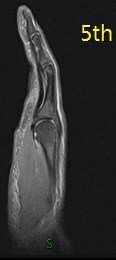

Annular pulley tears result in bowstringing of the tendon. Compare the sagittals of the 4th finger with the sagittal of the 5th finger which is not bowstrung (5th is labeled). I dont believe I have recognized only half of the pulley torn before.